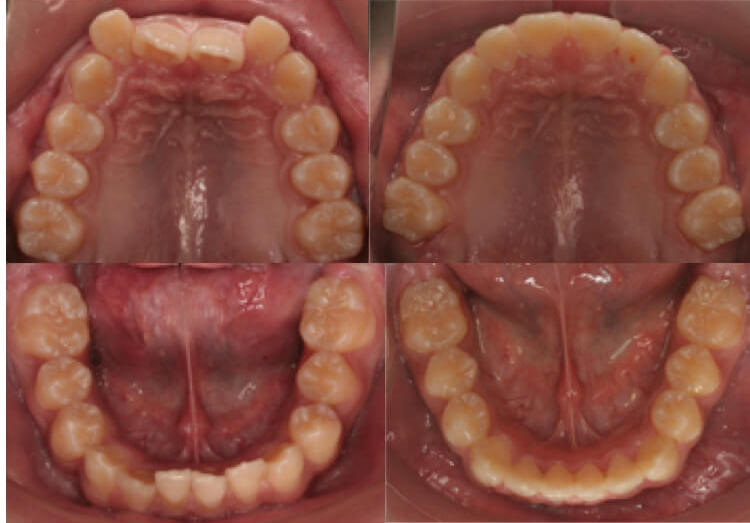

医学类型:深覆合, 牙列拥挤

矫正方法:固定矫正, 平导

治疗周期:18个月

这个男孩是15岁来我这矫正的,主诉是上嘴唇突出。

其实他是牙齿拥挤,伴有严重的深覆合,所以看上去下巴后缩,面下三分之一短,显得上嘴唇很突出。

我采用了不拔牙矫治,平导打开咬合,总疗程18个月后,男孩收获了帅气阳光的面容。